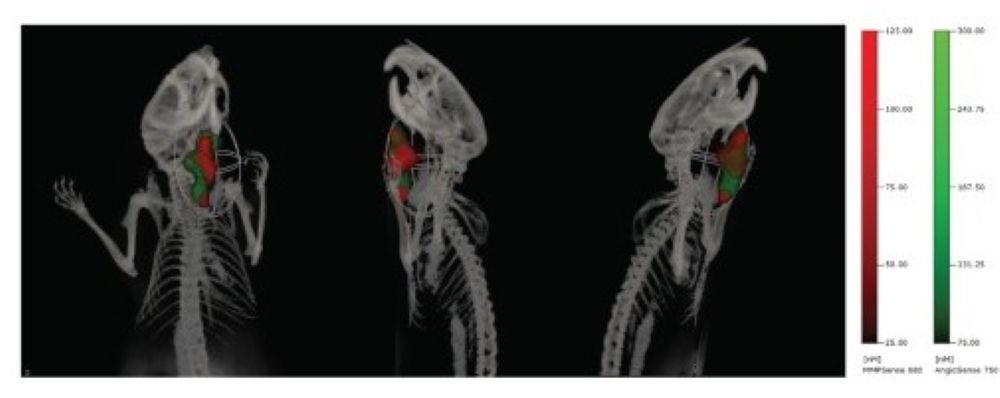

Optical imaging offers a non-invasive way to monitor processes involved in tumor growth and metastasis formation in immunodeficient mice. Here, fluorescence molecular tomography (FMT), with advanced 3D imaging, is used to delve deeper into the effects of hyperbaric oxygen therapy (HBOT) and radiation on tumor dynamics. By analyzing blood vessels with AngioSense and unraveling hypoxia with HypoxiSense probes, FMT provides a comprehensive view of the tumor environment. Seamlessly integrating FMT with CT imaging provides precise anatomical references. In this way, optical imaging methods can provide longitudinal insights into tumor properties, revolutionizing oncology research.

Fig. Effect of HBOT on tumor vasculature. Multimodal FMT/CT imaging of a FaDu-luc mouse 24 h after injection of MMPSense680 (red) and AngioSense750 (green) to detect tumor margins and region of tumor vascular leak, respectively.